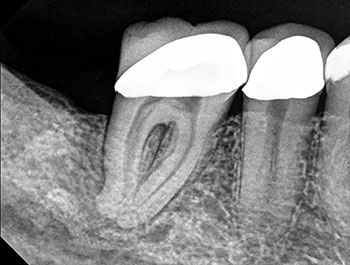

The patient returned in three months, when resolution of symptoms, healing of the deep probing defect and bone regeneration were confirmed. The tooth was obturated, and a foundational restoration was placed before the rubber dam was removed. Fourteen years of follow-up confirmed long-term periradicular health. The amount of appreciation and gratitude that this patient expressed reminds us that each individual tooth demands our best efforts.

Fig. 3: Recall PA.